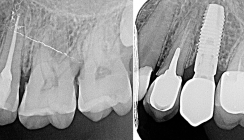

Wurzelkanalfüllung

Die Wurzelkanalfüllung eines c -förmigen Wurzelkanalsystems stellt eine weitere Schwierigkeit dar. Die erste Problematik ist die Form. Das Kanalsystem ist sehr unregelmäßig, aber die meisten Wurzelfülltechniken sind für runde Wurzelkanalformen produziert, wie Wurzelfüllstifte und Sealer. Mit der Technik der warm-vertikalen Kondensation lassen sich die gereinigten und desinfizierten Areale gut füllen. Durch ein langsames und vorsichtiges Einbringen des Wurzelfüllmaterials und einer guten Verdichtung sind Lufteinschlüsse vermeidbar. Es sollte darauf geachtet werden, dass das Wurzelfüllmaterial nicht überpresst wird.

Die neuen biokeramischen Wurzelfüllmaterialen sind gut für die Abdichtung der Kanäle geeignet. MTA lässt sich gut in kleinen Portionen in das Wurzelkanalsystem einbringen und gegebenenfalls mit Ultraschallaktivierung verdichten.